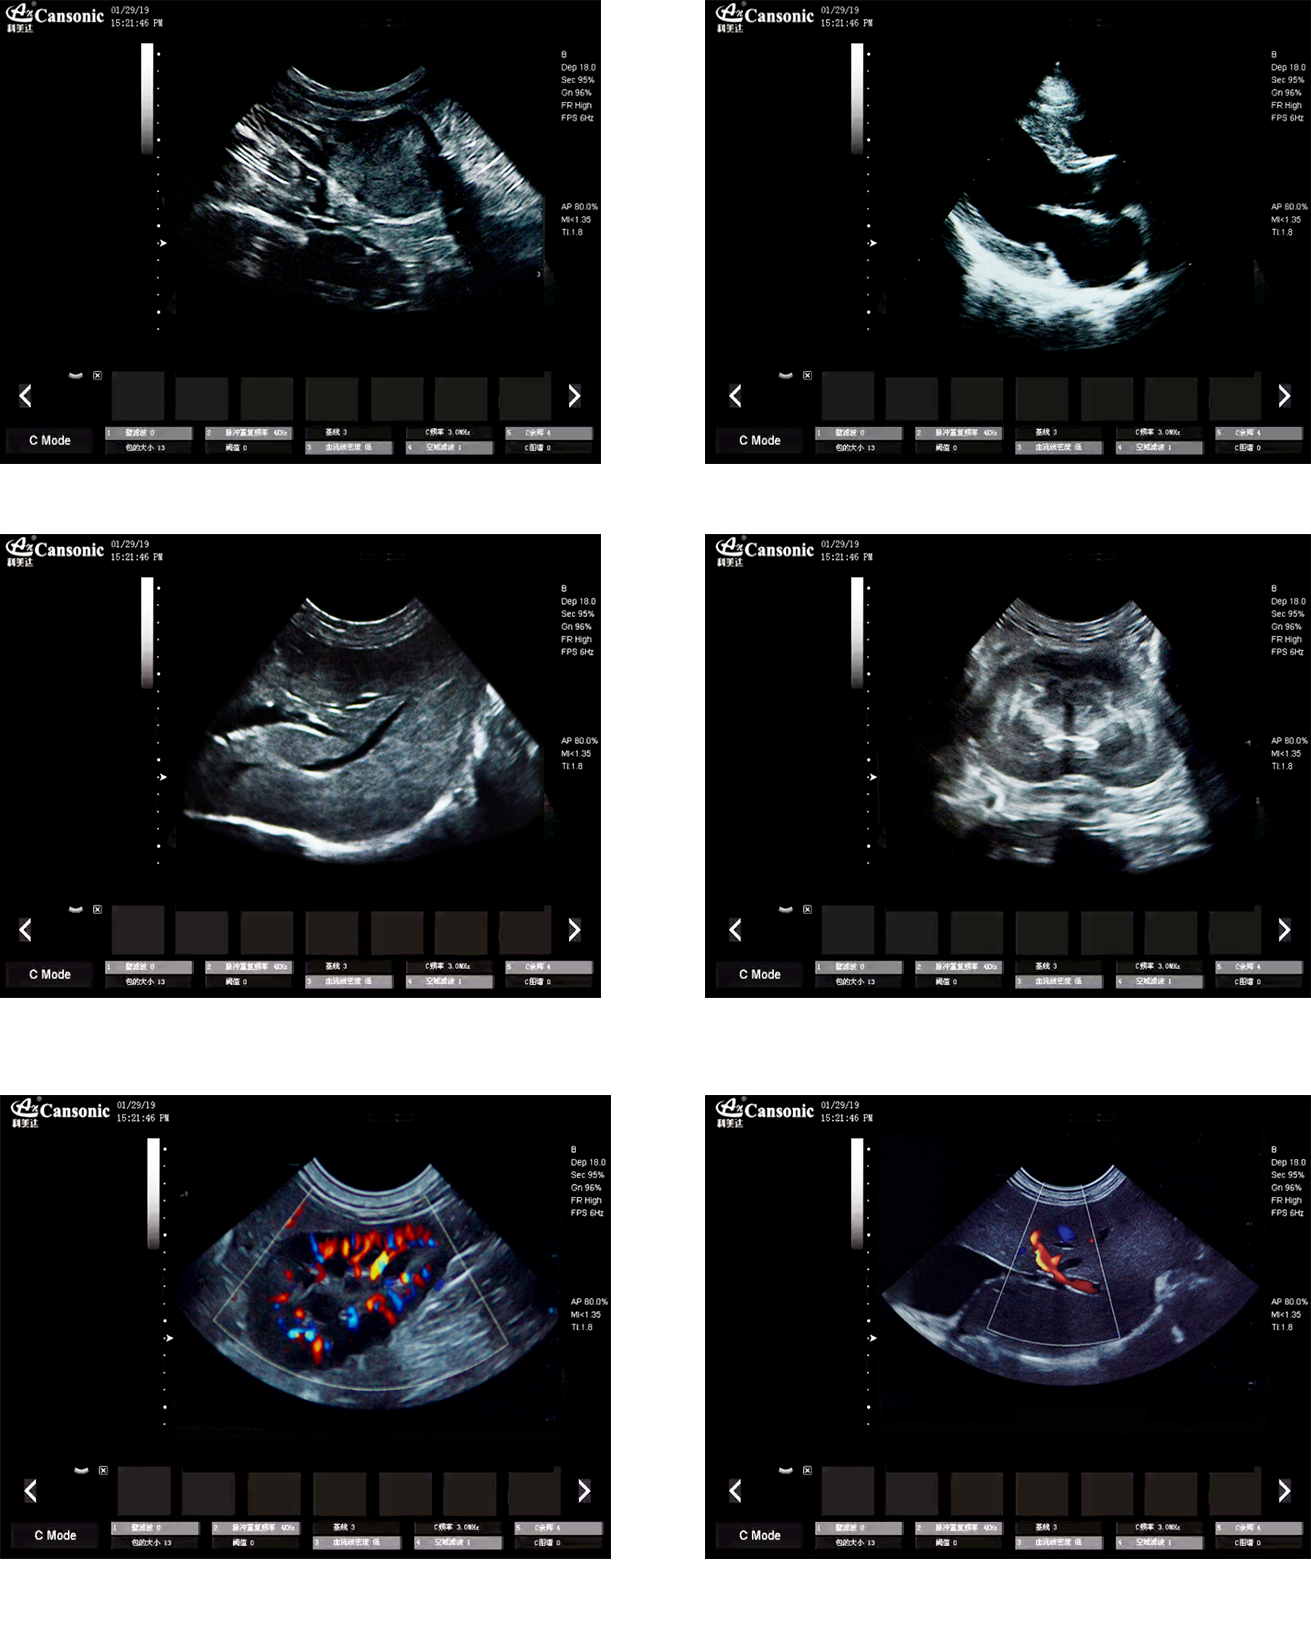

臨床圖示

1、薈萃高端彩超的專業(yè)技術(shù),各類型的專業(yè)獸用探頭,提供完整的動物臨床診療方案

2、專業(yè)的獸用彩超軟件,適合犬、貓、馬、牛、羊等各類大小動物彩超檢查

3、完備的獸用高端功能,能量多普勒POWER模式彩色多普勒Color成像模式

4、精準全數(shù)字濾波技術(shù),有效降低多普勒噪聲及運動偽像,提升多普勒超聲圖像